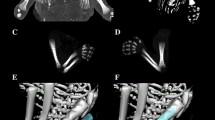

Using a Siemens–Biograph 128 mCT scanner (Siemens Healthcare GmbH, Erlangen, Germany) located at Department of Positron Emission Tomography and Molecular Imaging (Oncology Center, Collegium Medicum of the Nicolaus Copernicus University, Bydgoszcz, Poland), scans of fetuses in DICOM formats were acquired at 0.4 mm intervals, and subsequently subjected to morphometric analysis using the Medical Dicom Viewer-Osirix 3.9 software. Of note, Osirix 3.9 allows conducting any type of linear, planar and three-dimensional reconstructions of the studied objects along with their precise quantitative analysis (Fig. 1). The gray scale of achieved CT pictures expressed in Hounsfield units (HU) ranged from − 275 to − 134 for a minimum, and from + 1165 to + 1558 for a maximum. Thus, the window width (WW) altered from 1.404 to 1.692, and the window level (WL) varied from + 463 to + 712. The specifics of the imaging protocol were as follows: mAs—60, kV—80, pitch—0.35, FoV—180, rot. time—0.5 s., while the specifics of CT data were: slice thickness—0.4 mm, image increment—0.6 mm, and kernel—B45 f-medium. Of note, both WW and WL optimize the appearance of CT images by determining the contrast and brightness levels assigned to the CT image data. WW directly refers to the maximal number of shades of grey to be displayed on a CT monitor, and expressed by the range of HU. WL is referred to as the midpoint of the range of the CT numbers displayed (window center).

Measurements of the fibular shaft ossification center were performed in a specific order (Fig. 2). In each fetus, the assessment of linear dimensions, projection surface area and volume of the fibular shaft ossification center was carried out. On the right and left sides, the quantitative evaluation of the following six parameters of the fibular shaft ossification center was conducted:

length, based on the determined distance between the proximal and distal borderlines of the ossification center in the frontal plane (Fig. 2);

proximal transverse diameter, measured at the widest distance between the medial and lateral borderlines of the proximal region of the ossification center in the frontal plane (Fig. 2);

middle transverse diameter, measured at the widest distance between the medial and lateral borderlines of the central region of the ossification center in the frontal plane (Fig. 2);

distal transverse diameter, measured at the widest distance between the medial and lateral borderlines of the distal region of the ossification center in the frontal plane (Fig. 2);

projection surface area, based on the determined contour of the fibular shaft ossification center in the frontal plane (Fig. 2);

volume, calculated using advanced diagnostic imaging tools for 3D reconstruction, taking into account position and the absorption of radiation by bone tissue (Fig. 1d).